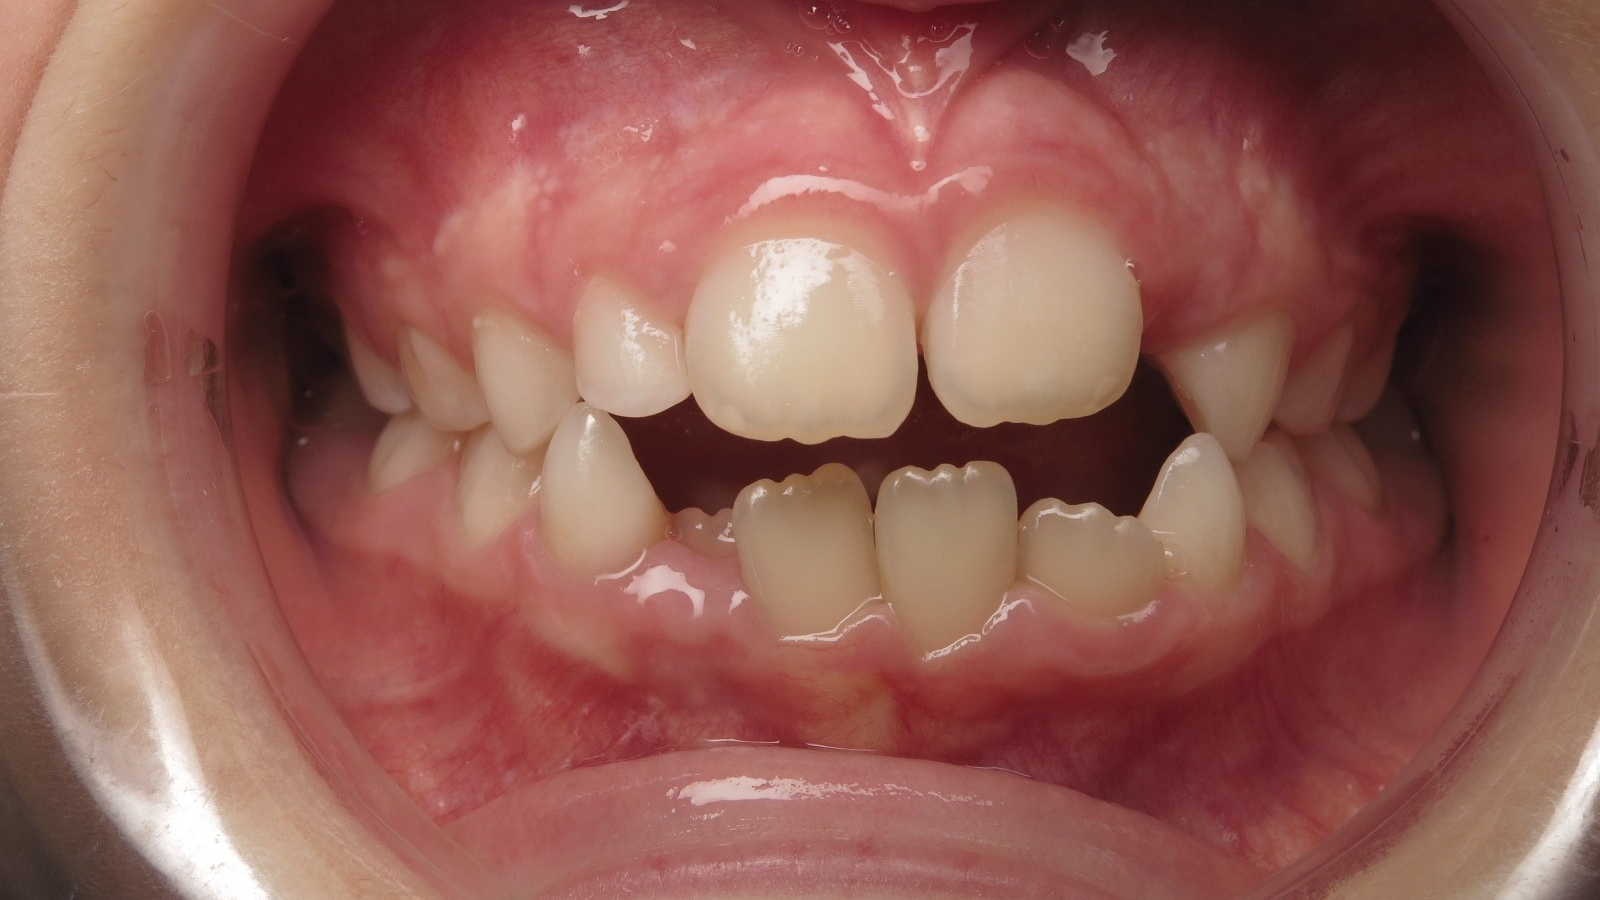

14 béance inversé gauche 5 ans

inversion postérieur coté droit et espace entre l'arcade du haut et du bas (béance)